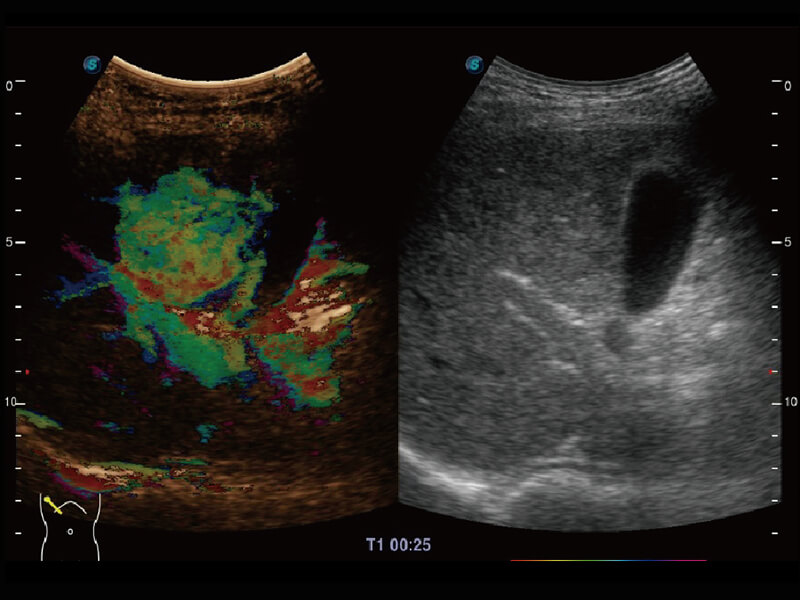

性能优异的硬件架构,极大提升超声系统的运行效率和数据处理能力。相比以往超声成像系统,Wis+平台为您带来极快的响应速度和成像帧频,提升检查流畅度。

S60探头工艺,从前端信号处理每一个环节采集无损声学数据,真实还原组织原貌,再现解剖细节。